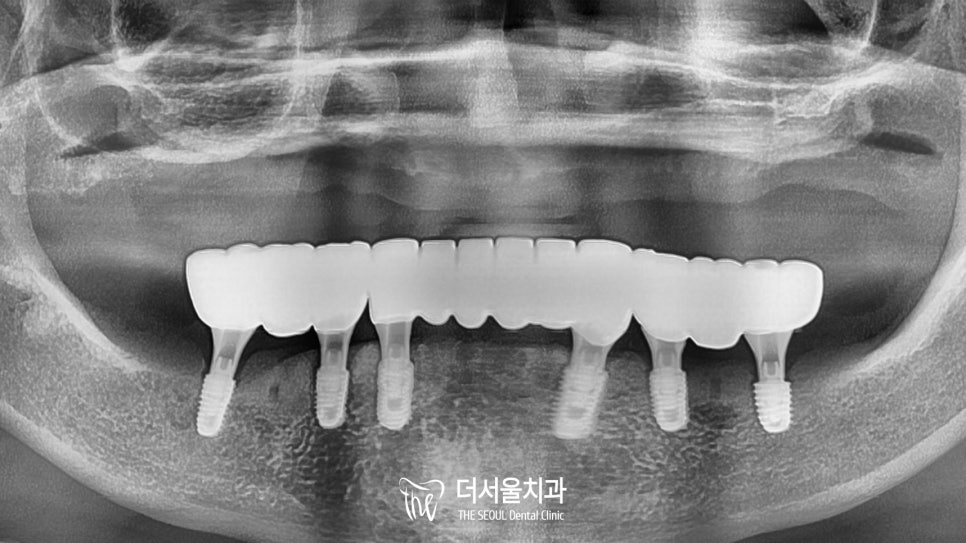

치료 계획을 세우기 전,

정확하게 파악하기 위해 엑스레이를 찍었습니다.

하악 전치부 치아들이 남아있었지만

이곳도 썩 좋지는 않았는데요.

기존에 근관치료를 받았던 밑으로

이차우식 및 염증이 생겨

동요와 치조골 소실이 관찰되었습니다.

따라서 더서울에서는

총 7개의 픽스처를 식립하여

개선을 도와드리기로 했습니다.

CT를 통해 확인해 보니 정확하게 심어져 있네요.